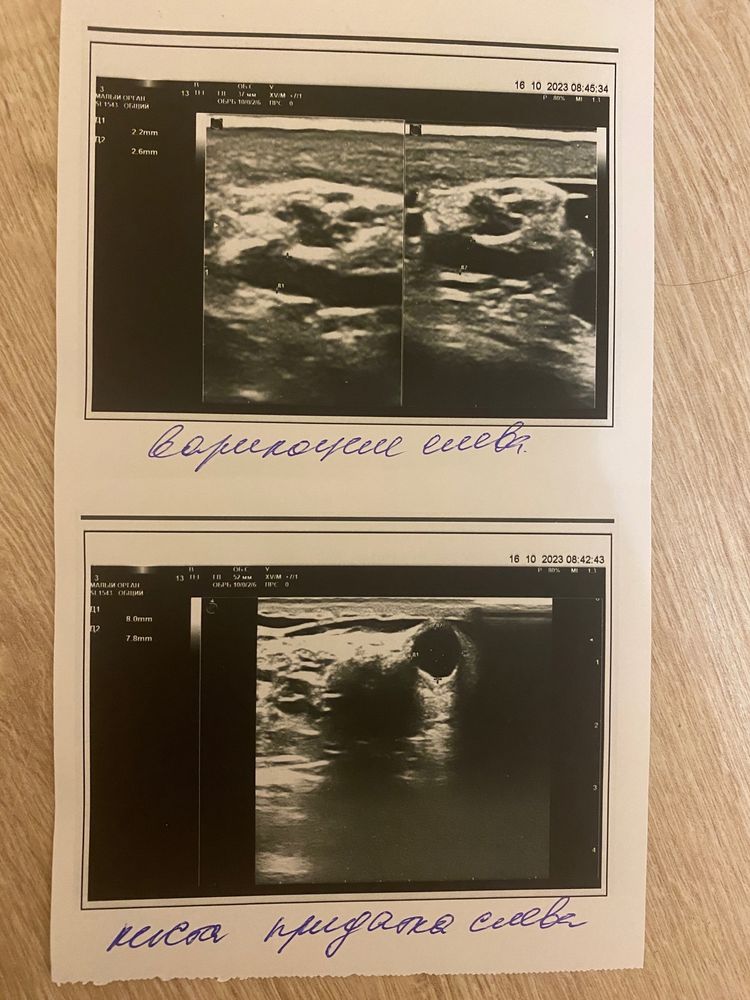

С детства диагноз варикоцеле, как и у всех мужчин в семье. Сходил на узи, сказали, что не так страшно и операция не нужна. После препаратов сдал спермограмму снова, но анализ не улучшился, даже ухудшился местами. Подскажите, что ещё можно сделать? Можно ли рассчитывать на естественную беременность? На 1 изображении спермограмма до лечения, на втором - после, третий снимок узи мошонки